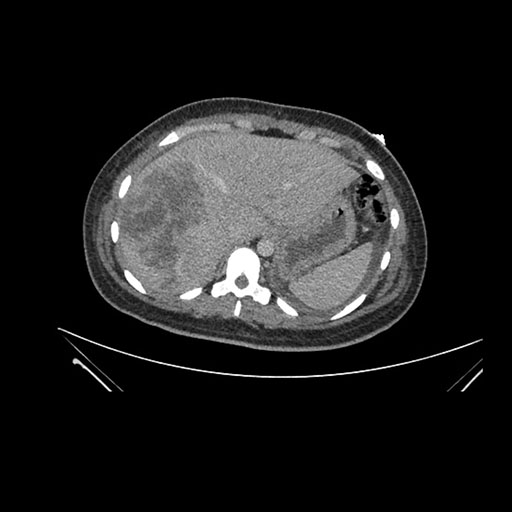

Axial Venous

Imaging analysis

Based on initial findings, which issue(s) would you be most concerned about?